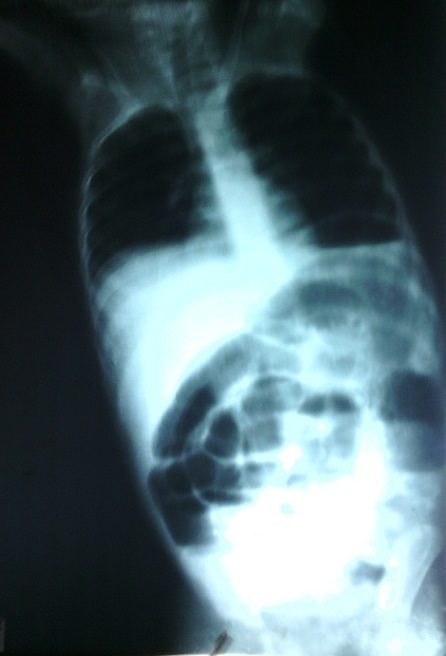

Il s'agit d'un garçon de 3 ans et 6 mois pesant 15 kg dont la symptomatologie remonte à 12 jours de l'intervention chirurgicale par des douleurs abdominales, une diarrhée liquidienne, la fièvre et l'anorexie. Il a été soigné en périphérie pendant 7 jours. Il y a reçu deux transfusions et une perfusion de quinine à des doses inconnues. Ceci sans amélioration de son état. Il est alors transféré au service de pédiatrie des Cliniques Universitaires de Lubumbashi avec le tableau clinique suivant: fièvre, obnubilation, urine d'aspect coca cola, sécheresse buccale, pas raideur de nuque, le pli cutané abdominal paresseux et sans plainte en rapport avec la sphère ORL. Des examens paracliniques dans le sang ont révélé: Hb 10,6g, Hte 33%, Groupe Sanguin O, Rhésus positif, glycémie 155mg. La goutte épaisse n'a pas été faite. Il a été traité pour neuropaludisme et fièvre bilieuse hémoglobinurique. Ce traitement était fait de 3 perfusions (sérum glucosé 5% 10ml/kg plus la quinine 10mg/kg) qui coulent chacune pendant 4 heures avec des intervalles de 4 heures entre elles. Une réhydratation faite d'un mélange de sérum glucosé 1L et Sérum physiologique 500ml lui est administré. Au premier jour d'hospitalisation il a émis des mélénas, présenté des convulsions tonico-cloniques (2 fois). Il était pâle et en coma stade II. Il a reçu comme traitement: diazépam 7mg en IM, Duphalac 1 sachet 3 fois par jour par la sonde nasogastrique. Une ponction lombaire a été réalisée mais l'analyse du liquide céphalorachidien n'a révélé aucune anomalie. Un cooling (siphonage de l'estomac avec du sérum physiologique ou de l'eau froide) a ramené du sans noirâtre. Au deuxième jour le patient était lucide, sans mélénas et sans convulsion. Le gavage par sonde nasogastrique était poursuivi. Au troisième jour il a présenté des vomissements alimentaires puis bilieux 5 fois, des douleurs abdominales, la soif et la non émission des selles et des gaz. Il avait des cernes oculaires, un ballonnement abdominale et le pli cutané abdominale était paresseux. Les examens de laboratoires ont montré: Hb 8,6g et glycémie 62mg/dl. Il a été réhydraté et a reçu Pedifen 10ml deux fois par jour. Au quatrième jour les signes de la veille se sont aggravés et Il a reçu le traitement suivant: perfusion de sérum physiologique 400ml + sérum glucosé 5% 600ml + KCl 45mEq pendant 6 heures et une canule rectale a été placée. La radiographie de l'abdomen sans préparation incidence face en position debout avait révélé la présence des niveaux hydroaériques plus larges que hauts prédominant au centre, une opacité dans l'hypogastre et la fosse iliaque droite (Figure 1). Ce qui a motivé son transfert en chirurgie. En chirurgie les plaintes sont les mêmes que celles présentées en pédiatrie. Les signes vitaux montrent une tachycardie à 123bpm, une fréquence respiratoire à 30 cycles par minute et la température à 36,8°C. Le patient est léthargique, avec cerne oculaire, pâleur des conjonctives, sécheresse buccale et une sonde nasogastrique qui ramène un liquide fécaloïde.

Figure 1.

Radiographie de l'abdomen à blanc qui montre des niveaux hydroaériques centraux plus larges que haut et une dilatation importante du grêle rempli de gaz prédominant dans la fosse iliaque gauche, le flanc gauche, l'hypochondre gauche. Une opacité hypogastrique et dans la fosse iliaque droite